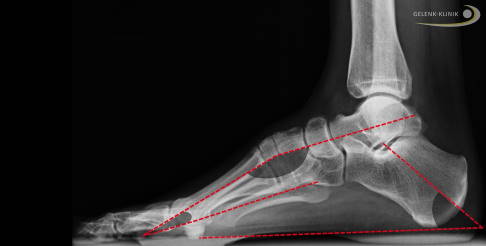

Durch die typische Abfolge der Muskelschwächung entsteht am häufigsten ein Hohlfuß (Pes excavatus). Besonders typisch ist der sog. innere oder mediale Ballenhohlfuß. Er wirkt sich im weiteren Verlauf durch seine besondere Belastung im Vorfuß auch auf das Sprunggelenk und den Rückfuß aus.

In der frühen Krankheitsphase ist der außen am Fuß ansetzende Musculus peroneus brevis, also der kurze Wadenbeinmuskel, betroffen. Dieser Muskel ist ein Antagonist (Gegenspieler) des hinteren Schienbeinmuskels. So resultiert aus der Schwäche des außen ansetzenden Muskels eine Fehlstellung mit vermehrtem Zug des Fußes nach innen. Diese Stellungsanpassung erfolgt im Gelenk vor dem oberen Sprunggelenk, also im Chopart-Gelenk. Der Fuß stellt sich hier von oben gesehen mehr nach innen ein (Supinationsstellung).

Bei dieser Schwächung kommt es auch zu einem Ungleichgewicht zwischen den beiden Wadenbeinmuskeln M. peroneus longus und brevis. Daher überwiegt bei der Schwächung des außen ansetzenden kurzen Wadenbeinmuskels (M. peroneus brevis) die Kraft des langen Wadenbeinmuskels (M. peroneus longus), der von außen unter dem Fuß hindurch unten, innen am Mittelfuß ansetzt. Dieses Ungleichgewicht führt zu einer vermehrten Senkung des ersten Mittelfußknochens. Der Fußaußenrand wird durch die mangelnde Muskelführung nicht mehr geführt und verliert die Kontrolle (Steilstellung des 1. Strahles).

Therapieprinzip bei Fehlstellung des Fußlängsgewölbes

Im Hinblick auf eine aus der langjährigen Fehlstellung des Hohlfußes häufig resultierende Arthrose des Sprunggelenkes können weitere Operationen sinnvoll sein. Eine Begradigung von Schrägstellungen steht bei diesen Methoden immer im Vordergrund. Schiefe Achsen sind, wenn symptomatische Arthrosen vorhanden sind, immer ein Grund für eine Korrektur. Diese ermöglichen häufig eine kausale (ursächliche) Therapie und eine vorübergehende Besserung der Sprunggelenksarthrose. Leider sind Arthrosen, die einmal entstanden sind, nicht mehr zu heilen. Sie schreiten aber nach solchen Maßnahmen oft langsamer fort.